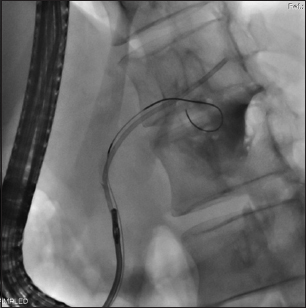

Complete retrieval of PMPSs and stent fragments was possible in 12 (75%) patients. In 8 patients (50%), the stents could be retrieved using grasping forceps (Fig. 1,2). In 1 patient the PMPS was retrieved using a combination of extraction balloon and grasping forceps, whereas in 1 patient the stent could be retrieved using a novel endoscopic ultrasound-guided extrusion method and snare [13]. In 2 patients, where all the conventional techniques for stent retrieval failed, the stents were retrieved using a pancreatoscope (Fig. 3). Despite the use of multiple endoscopic accessories (grasping forceps, snare, extraction balloon and Soehendra stent retriever) the stent/fragments could not be retrieved in 3 (18.75%) patients. All these 3 failures were during the initial 7-year period of the study, when the SpyGlass pancreatoscope was not available in our unit. One of these 3 patients underwent surgical removal of the stent, whereas the other 2 patients refused surgery.

Figure 1 Endoscopic removal of proximally migrated stent lodged at genu using grasping forceps

Figure 2 Endoscopic removal of proximally migrated fragmented stent using grasping forceps